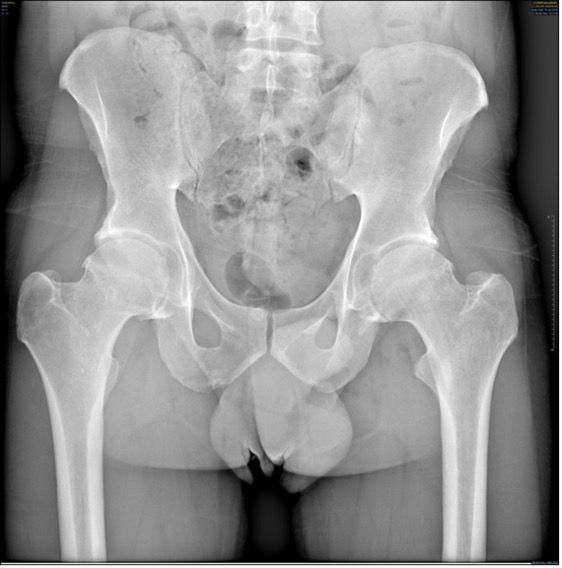

Hips in coxa vara sometimes present a very significant femoral offset which may be prove to be difficult to restore using standard stems. In this case, a varus-tilted or lateralized stem should be used and this will require a very low femoral cut, often with loss of residual femoral offset and a risk of lengthening the lower limb. Positioning a straight cementless stem in varus runs the risk of trajectory error and femoral pain. If a modular neck implant is chosen, the increased lever arm results in significant pressures on the modular neck and neck-head junction with risks that are already known. Finally, even with a cemented stem, positioning it in varus will increase the pressures on the bone-cement interface, with a risk of early loosening. With calcar-guided short stems, the stem will follow the medial cortex of the neck (which will have been cut high), naturally finding a varus tilt and making it possible to reproduce even very significant offsets (Figs 4 and 5).

In total hip replacement, there is often a relative reduction in the acetabular offset due to burring off a few millimetres, which is necessary for the implant to fit in the hip socket cavity, and this is compensated for by a relative increase in femoral offset, to restore the overall hip offset.